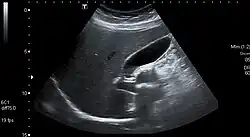

Abdominal ultrasonography showing gallbladder and common bile duct

The gallbladder varies in size, shape, and position among different people.[2] Rarely, two or even three gallbladders may coexist, either as separate bladders draining into the cystic duct, or sharing a common branch that drains into the cystic duct. Additionally, the gallbladder may fail to form at all. Gallbladders with two lobes separated by a septum may also exist. These abnormalities are not likely to affect function and are generally asymptomatic.[8]

The location of the gallbladder in relation to the liver may also vary, with documented variants including gallbladders found within,[9] above, on the left side of, behind, and detached or suspended from the liver. Such variants are very rare: from 1886 to 1998, only 110 cases of left-lying liver, or less than one per year, were reported in scientific literature.[10][11][2]